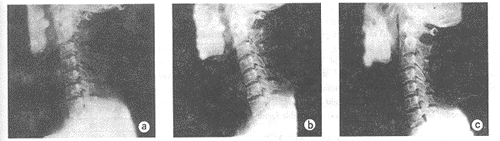

2.3 牵引时按病变的部位不同,牵引角度不同,而拉伸间隙亦不同,如本组患者皆是颈椎 曲度变直,故按照上颈椎牵引角度为后伸5°~20°,C4~5为0°,C5~6为前 屈5°~10°,C6~7为前屈15°时,其间隙拉的最大,其拉伸长度在0.1cm~0.3cm 之间,而牵引在此重量下拉伸的部分只有椎间隙,而椎体无拉长(图1)。

图1a 牵引前C5~6椎间隙0.1cm;

图1b 牵引力为体重的20%,角度为5°,C5~6椎间隙0.35cm

图1c 牵引前,C6~7椎间隙为0.1cm

图1d 牵引力为体重的20%,角度为15°时,C6~7椎间隙为0.4cm

图1 不同牵引角度治疗颈椎病X线观察